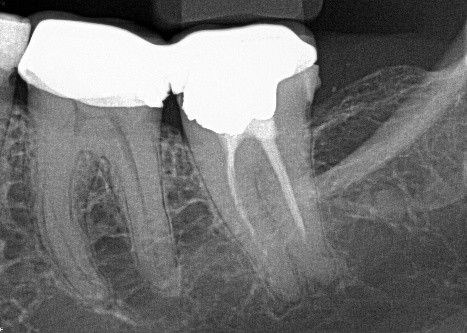

3. (Select ONE OR MORE correct answers)

What observation(s) can be made for tooth 1.5?